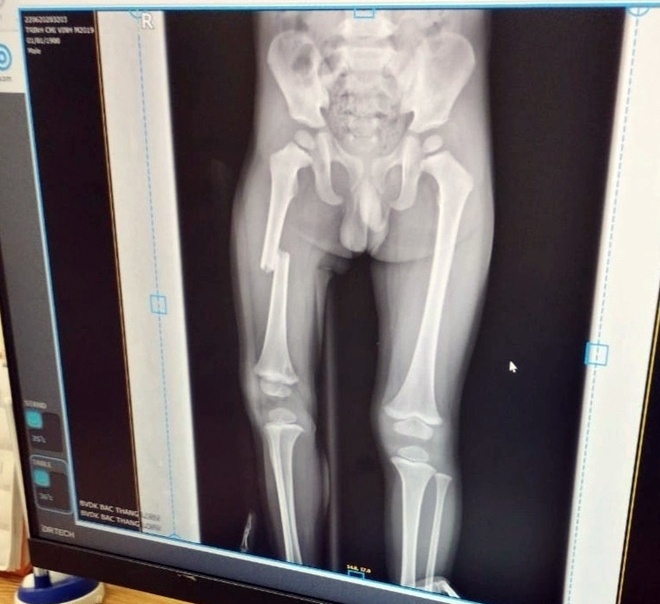

Dap gay xuong dui anh 1

Ảnh gia đình cung cấp về kết quả chụp X-quang xương chân cháu bé.